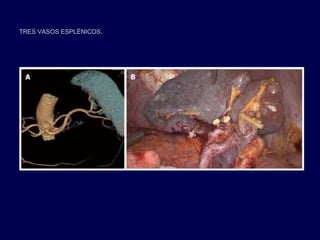

A: LA EVALUACIÓN PREOPERATORIA DE LA ANATOMÍA VASCULAR ESPLÉNICA MEDIANTE TOMOGRAFÍA

COMPUTARIZADA CON IMÁGENES IMÁGENES 3D; B: VISTA OPERATIVO DESPUÉS DE LA FINALIZACIÓN DE

LA DISECCIÓN DE LOS GANGLIOS LINFÁTICOS DEL BAZO

TRES VASOS ESPLÉNICOS.

• La identificación de los vasos esplénicos es crítico en

preservación laparoscópica de bazo.

• La técnica laparoscópica tiene limitaciones significativas:

– Siendo esencialmente de dos dimensiones con una

pérdida de la percepción de profundidad y la

orientación espacial

• Evaluación 3DCT preoperatoria de la anatomía ayuda a

la ligadura segura y rápida, y la disección de los

linfonodos hiliares esplénicos, especialmente en los

pacientes obesos.